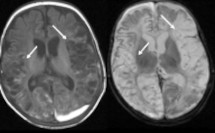

Un approccio clinico all’ipotono neonatale attraverso i casi

Castaldo B, Cossovel F, Starc M, Bua J, Travan L.

Una guida semplice sui segni clinici dell’ipotono, sulle ipotesi di diagnosi e sugli esami essenziali da non dimenticare. Può essere la manifestazione di varie condizioni, alcune gravi.